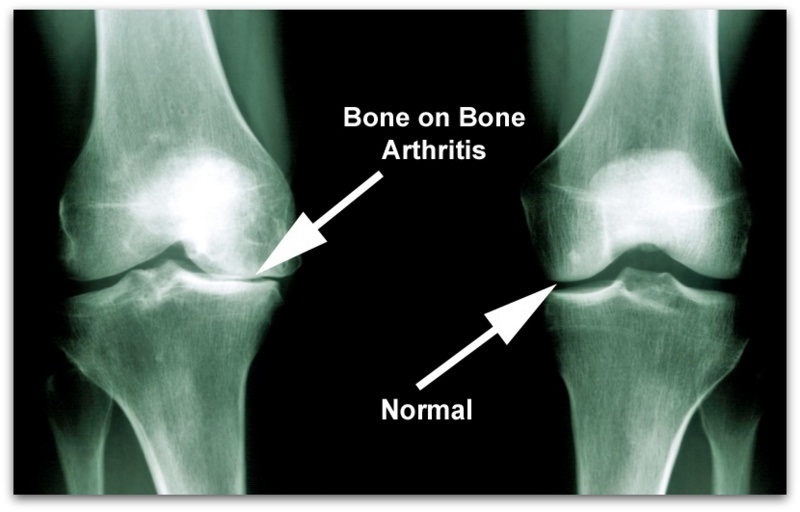

Распространетоста на артритисот на коленото во Соединетите Држави е двојно зголемен кај возрасните од Втората светска војна. Во моментов во Соединетите Држави, речиси 20 отсто од луѓето постари од 45 години страдаат од остеоартритис на коленото.

Поради начинот на кој остеоартритисот на коленото се манифестира во човечкото тело, при што коските во коленото се тријат директно една со друга за да формираат полирана површина, истражувачите можеа да ја проценат неговата распространетост во три главни временски периоди: праисториски, ран индустриски период и модерно постиндустриски.